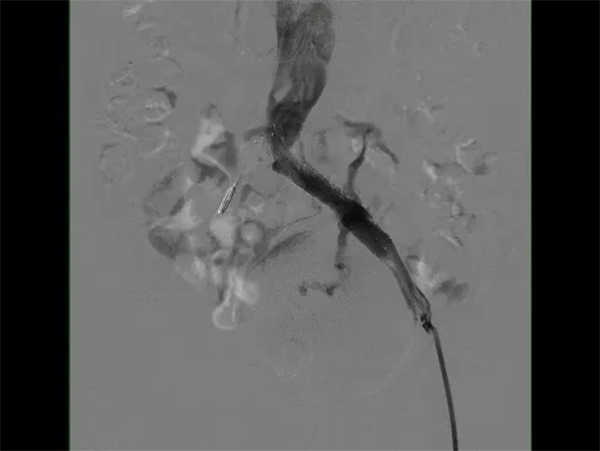

在與患者及家屬進(jìn)行了詳細(xì)的交流后,患者決定住院治療。在經(jīng)過了詳細(xì)的病情分析后,介入科肖晉昌團(tuán)隊(duì)為其制定了“髂靜脈造影+球囊擴(kuò)張+支架置入”的治療計(jì)劃。術(shù)中造影發(fā)現(xiàn)患者左髂總靜脈近心端重度狹窄,周圍側(cè)支開放,狹窄兩端壓差明顯,均提示患者存在重度的髂靜脈壓迫(圖3)。予以球囊擴(kuò)張狹窄處(圖4),然后行支架置入(圖5)。支架置入后造影患者左髂靜脈血液回流明顯改善,周圍側(cè)支減少。術(shù)后由張科醫(yī)師負(fù)責(zé)對(duì)其隨訪,經(jīng)過1個(gè)月的隨訪,患者目前下肢潰瘍基本愈合(圖6)。

圖5 支架置入